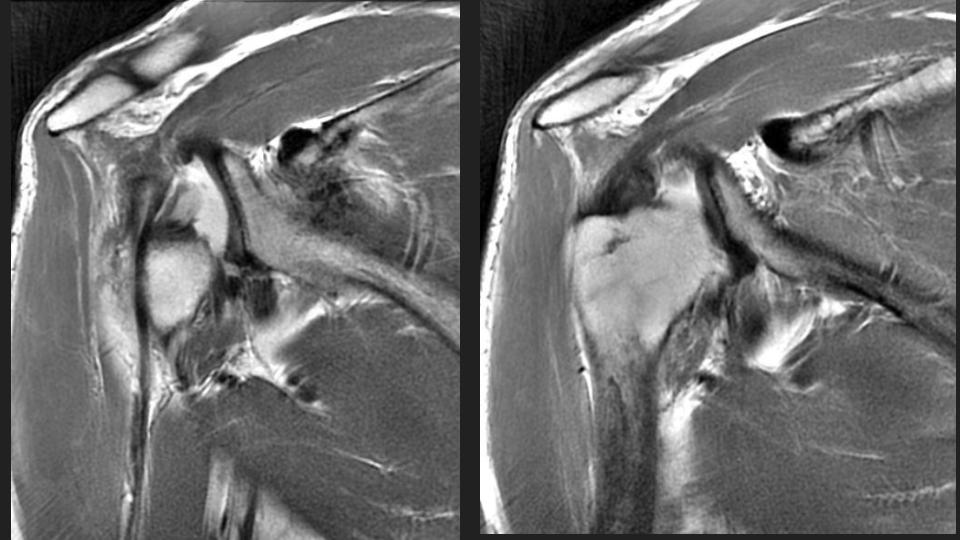

36M with chronic pain and limited motion 3 years after work related injury

My colleague had to share this with me after a failed attempt at arthrography. He puts the shoulder in Grashey, but it doesnt really look like Grashey. No matter what, he couldnt get in and converted it to a routine MRI. The first set of Cor images look so nice....or do they? The crazy thing is that the injury was 3 years ago. Not all workers comp is bogus. I was taught the posterior shoulder dislocation locks the shoulder in internal rotation, but based on the axial image, it is not. 1) Why is that? 2) I think thats partly why the scout image for the arthrogram was so misleading.

dislocation ( RID4770 )